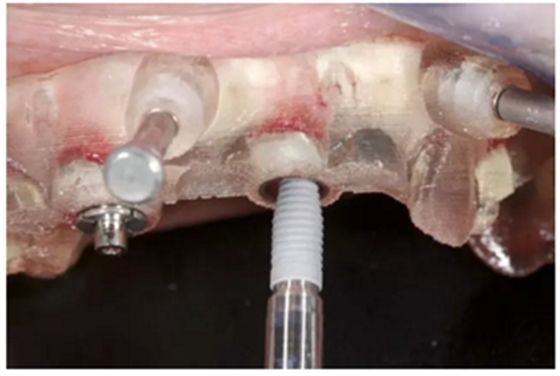

通過固位釘固定上頜NobelGuide外科導(dǎo)板和第一枚已植入的植體和導(dǎo)板基臺。

4枚NobelReplace CC RP4.3植體(11.5mm 軸向植體和13mm 傾斜植體)已植入完成:前牙區(qū)植體上裝配的是導(dǎo)板基臺,后牙傾斜植體上裝配的是內(nèi)錐形連接的引導(dǎo)式持釘器。